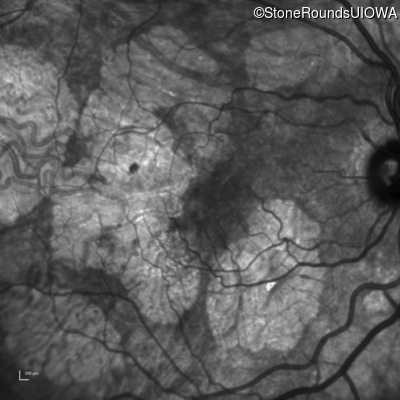

Infrared Fundus Photograph - Left - 20/40 +1

Exemplar